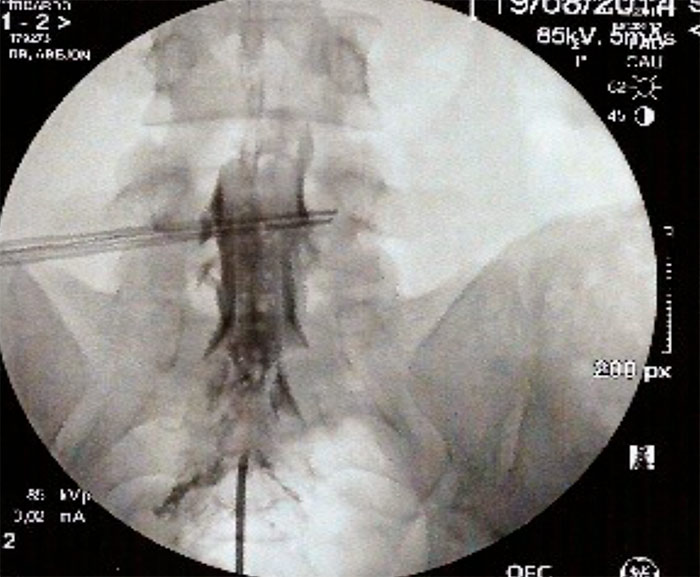

Con el paciente en decúbito prono y una almohada en la zona pelvica se coloca el  arco de fluoroscopia en posición AP. Con un marcador radiopaco se localiza la línea media y se gira el  arco de fluoroscopia en posición lateral. Una vez localizado el target deseado, que es el hiato sacro, se infiltra con anestésico de piel y tejido celular subcutáneo, ligamento sacrocoxigeo y periostio. Se realiza la punción con aguja de Tuohy bajo visión continúa hasta atravesar el ligamento sacrocoxigeo y se redirige la aguja en sentido craneal. Se administrará contraste radiopaco bajo visión continua y se comprobara su distribución. Para comprobar la distribución del contraste se coloca el arco de fluoroscopia en posición anteroposterior (árbol de navidad), y posteriormente se inyecta de la medicación (AL y Corticoides), y retirada de la aguja con el mandril.

Con el paciente en decúbito prono, se coloca una almohada a la altura de la pelvis para corregir la lordosis fisiológica, y el arco de fluoroscopia en posición AP , con el  marcador radiopaco se localiza la línea media, se gira el arco de fluoroscopia a posición lateral para localizar el hiato sacro. Una vez localizado se infiltra con anestesia local de la piel, tejido celular subcutáneo, ligamento sacrocoxigeo y periostio, y se realiza punción con una aguja introductora con visión continúa hasta atravesar el ligamento sacrocoxigeo, se  administra contraste radiopaco (2-5ml) en visión continua y se comprueba su distribución. Posteriormente se vuelve a comprobar la distribución del contraste con el arco de fluoroscopia en posición anteroposterior (epidurografía). La epidurografía nos permitirá identificar las raíces que no se rellenan con contraste (fibrosis).